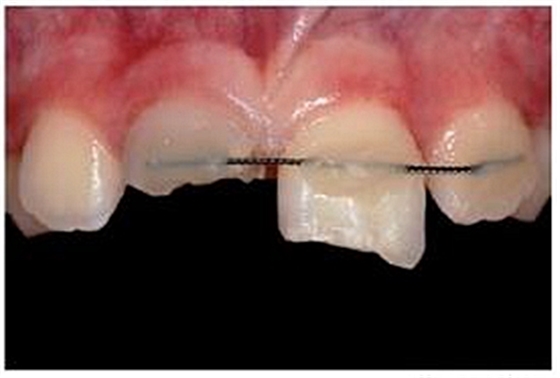

一位九歲男孩在騎車時(shí)不慎摔倒而導(dǎo)致牙齒外傷。受傷后立即進(jìn)行了應(yīng)急處理,首先對(duì)折裂的中切牙進(jìn)行牙髓治療、并對(duì)松動(dòng)脫位的左側(cè)中切牙進(jìn)行活動(dòng)夾板固定(21)。受傷后兩周,患者前來(lái)就診,要求行兩側(cè)上中切牙的后續(xù)治療,并咨詢能否及如何修復(fù)右側(cè)斷裂的中切牙(11)。

專業(yè)醫(yī)師對(duì)患者進(jìn)行了仔細(xì)檢查及診斷分析。11被診斷為冠根折伴牙髓暴露及大面積牙體缺損。21被診斷為側(cè)向移位伴冠折。檢查活動(dòng)夾板在位,兩中切牙根管治療術(shù)中,氫氧化鈣根管內(nèi)封藥。11明顯變色。11用Cavit暫封,21復(fù)合樹(shù)脂充填。11腭側(cè)頸部有一折裂片。